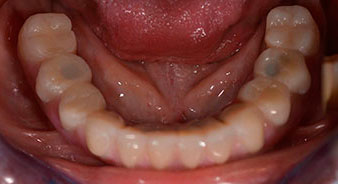

Die 64-jährige Patientin wurde mit einer Unterkiefer-Restbezahnung 38, 33 und 43 und einer klammerbefestigten Interimsprothese im Unterkiefer vorstellig (Abb. 1 und 2).

Die notwendige parodontologische Behandlung und Extraktion im Oberkiefer sollte zu einem späteren Zeitpunkt erfolgen, da die Patientin Lehrerin ist und zu dem Zeitpunkt mit Abiturprüfungen beschäftigt war. Sie konnte weder essen noch adäquat sprechen, da die Interimsprothese sehr häufig und bei der kleinsten Belastung brach.